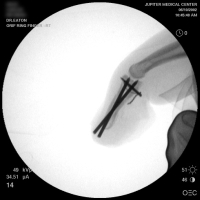

| A midline longitudinal palmar approach was used. This view shows a transverse pin across the dorsal proximal fragment, to be used as a path for interosseous wiring. Additional pins have been placed across each single cortex for later advancement. |

| A wire was passed through the dorsal proximal pin track and then around the palmar pins. After reduction and tightening this wire, the pins were advanced to engage the dorsal cortex. |

| Wiring was used to offset the strong pull of the flexor insertion. |

| All pins were cut below the surface of the skin. |